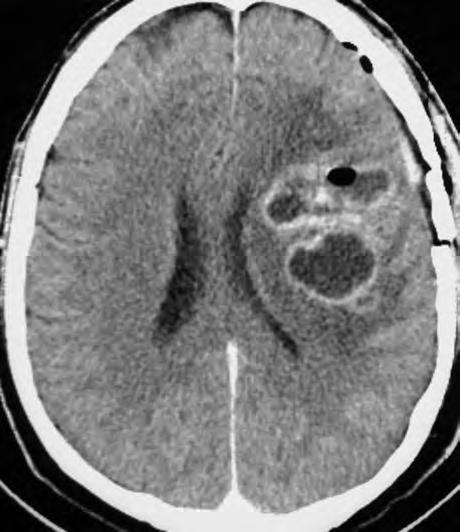

Obr. 1.1 Glioblastom, stav po kraniotomii, CT obraz po i.v. aplikaci kontrastní látky ukazuje heterogenní, expanzivně se chovající útvar s útlakem a přetlakem postranních komor a posunem středočárových struktur. Tvar je nepravidelný – na jednom řezu klamně působí jako multifokální. Rozpadlé centrum je ohraničeno prstenčitou zónou zvýšeného enhancement (hyperdenzity) po aplikaci k.l. i.v. představující oblast nádoru s porušenou hematoencefalickou bariérou –šipka bílá. Okolí útvaru je ovládnuto hypodenzním perifokálním edémem, který však obsahuje nádorové buňky – šipka čárkovaná. Hranice edému představuje prakticky hranici nádoru.

CT nebo MR vyšetření je podstatné vědět, že vnativním zobrazení nemusí být tumor vždy zřetelný, proto je nutné provést vyšetření spoužitím kontrastních látek. Výsledek zobrazovacího vyšetření může svelmi vysokou pravděpodobností informovat opřítomnosti maligního expanzivního ložiska viz obr. 1.1., 1.2., 1.3. Takovýto nález je dostatečnou indikací koperačnímu zákroku. Vdětském věku je možné provést ultrasonografické vyšetření mozku.